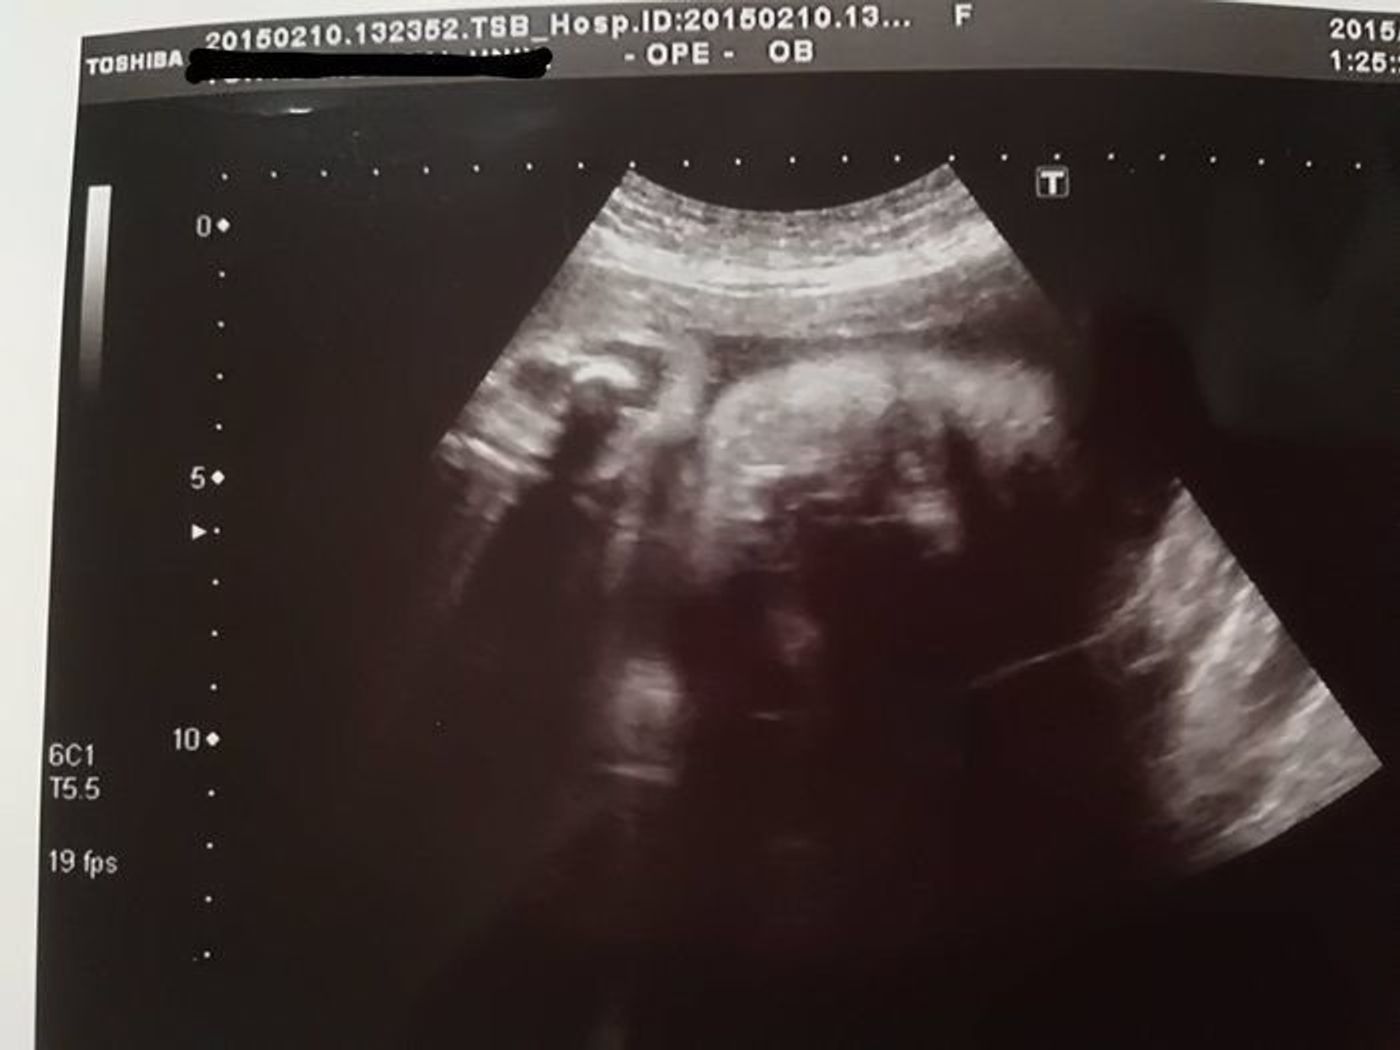

産まれた直後と妊娠28週目のエコー写真の比較です。 左:産まれた直後 右:妊娠28週目 このような写真が枚、それ以外に約8分間の動画をDVDで貰えました。超音波 (エコー) 検査で胎児の頭部や腹部、大腿骨などを計測します。こ れを胎児計測と呼んでいます。 推定児体重:胎児計測の結果から推定児体重(EFW estimated fetal weight) を計算することができます。胎児は妊娠の進行とともに成長します。発育の具 合を評価するためには、妊娠週数ごとに(06年 胎児心エコーガイドライン作成委員会編) •胎児心臓スクリーニング(レベルⅠ) –原則としてすべての妊婦が対象 •胎児心精査(レベルⅡ) –診断確定のために胎児心疾患に精通した医師が 精密

超音波エコー写真妊娠後期 (妊娠28週目~妊娠35週目) 妊娠後期 (28週目~35週目)の超音波エコー写真を紹介します。 東京都立川市 井上レディスクリニック院長。 産婦人科専門医、日本乳癌学会認定医、認定健康スポーツ医 他。 診療のかたわら、思春期から更年期の様々な女性に対しての講演活動、また、雑誌・TVなどに、出演、監修、執筆するなど多方面で今回の妊娠は切迫流産で入院などトラブル続きでしたがやっと28週目です! 何度も4Dエコーをしてもらっていますがいつもお顔を隠していたのですが今回はばっちり見せてくれました。 横顔がパパそっくりでとても可愛い~(^^) 鼻が高いのもパパに似てくれますように! 5人目にして女の子が確定しているのでお兄ちゃん達は産まれてくるのを凄く楽しみにしてます♪ 確か29週ぐらいだったと思います。 エコーに映る我が子を見てショックを受けました。 たばかりの赤ちゃんは顔も小さめで、鼻や口などのパーツが大きめには見えますが、エコー の方が鼻も口も、実物よりも大きく写っているように見えますよね。 さらに言えば、3Dエコーよりも4Dエコー

妊娠10週の胎児の体重や母体の様子看護師が解説 18年5月27日 妊娠3ヶ月のエコー写真の様子 妊娠6週頃の赤ちゃんはとても小さくエコーではわかりにくく、心拍はまだ確認できません。 まだ胎盤ができてないので卵黄嚢から栄養をもらっています。 妊娠3いる.胎児活動性はHypoxiaにより著明に減少する.母体による胎動記録法の中で最も 普及しているのは,Pearsonらのcounttoten胎動表であり,妊婦は午前9時より胎 (4)クリニカルカンファレンス(2);胎児評価を考える 2)エコーによる胎児機能評価妊娠28週(妊娠8ヶ月)のエコー写真・超音波写真 妊娠28週目:受精から1~1日目 胎児の大きさ:頭殿長(座高)が39~40cm 胎児の体重:1000~1300gほど 母体の変化:頻繁なお腹の張り・頻尿・血圧の上昇 妊娠28週(28w)に入ると、胎児の身長が伸びるペースはこれまでと比べると、ちょっとスローペースに。 皮下脂肪がついて丸みを帯び、皮膚のしわがなくなって

妊娠28週 胎児の体重 赤ちゃんの聴覚がほぼ完成します 妊娠28週 胎児体重は正常発育児954%が853g~1474g 平均体重:1163gです。※1 少しずつ成長していた聴覚が、28週目にはほぼ完成します。外部の音もよりハッキリと感知できるようになりますし、胎教を始めるにはうってつけの時期なの ほとんどの器官が完成し、機能の練習を始める 妊娠29週を含む妊娠8ヶ月の赤ちゃんは大きさが40cm前後、推定体重は1000~1500gほど。 成長が目覚ましく、ほとんどの器官が完成する時期です。 出典: featurecozrejp 脳や心臓、肺など中枢神経から内臓器官の機能が完成に近づきます。 加えて、聴く練習や見る練習、呼吸の練習も始まります。 詳しくはこちらの記事を 妊娠28週目(28w0d~6d)のエコー写真とエピソード|妊娠8ヶ月 妊娠28週目は妊娠8ヶ月の第1週にあたり、ここから妊娠後期に入ります。 出産予定日にどんどん近づいてきましたね。 ママのお腹はさらに大きくなり、前にせり出してくる頃です。 足元が見えにくくなるので、転倒などには十分気を付けましょう。 赤ちゃんの体は体重が1kgに到達するくらいの大きさに